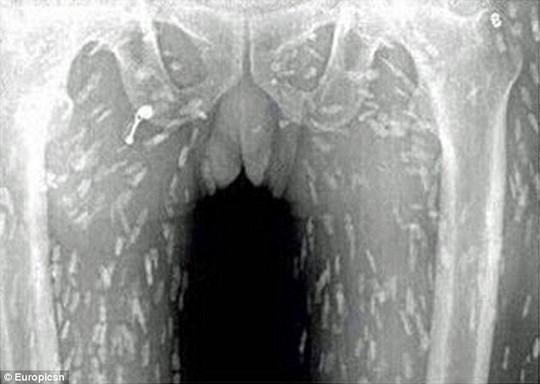

Sán xuất hiện khắp cơ thể người đàn ông

Trước đó, người này đã đến bác sĩ khám và than phiền về việc đau bụng, ngứa da. Kết quả quét toàn bộ cơ thể cho thấy sán dây ký sinh trên khắp cơ thể của bệnh nhân. Người này cho biết trong thời gian dài, anh là tín đồ của món sashimi (cá sống). Do đó, các bác sĩ tin rằng nguyên nhân người đàn ông nhiễm sán là do ăn quá nhiều cá và thịt chưa nấu chín kiểu Nhật.